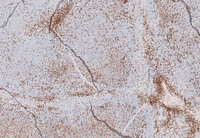

Figure 8: IgG and CD21 in Splenic Marginal Zone Lymphoma

The lymphoma cells are positive for IgD (pictured on the left). Most marginal zone lymphoma of splenic origin (as compared to nodal marginal zone lymphoma) are more likely to be positive for IgD.

CD21 immunostain (pictured on the right) highlights markedly expanded and tight follicular dendritic cell meshworks within the lymphoma nodules.